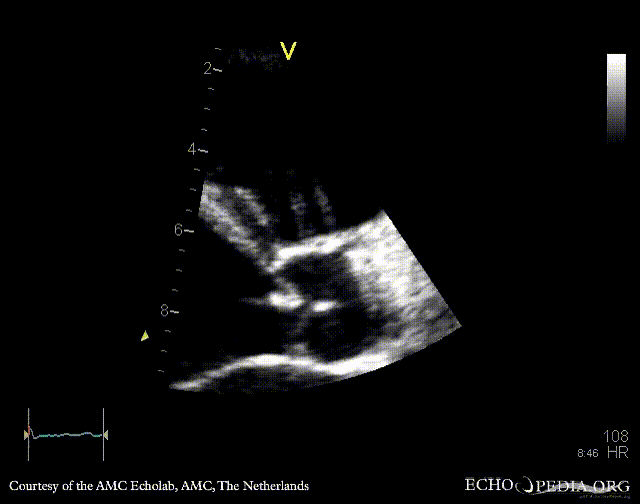

PLAX: dilated left ventricle, poor function, vegetation on aortic valve PLAX with zoom: vegetation on aortic valve